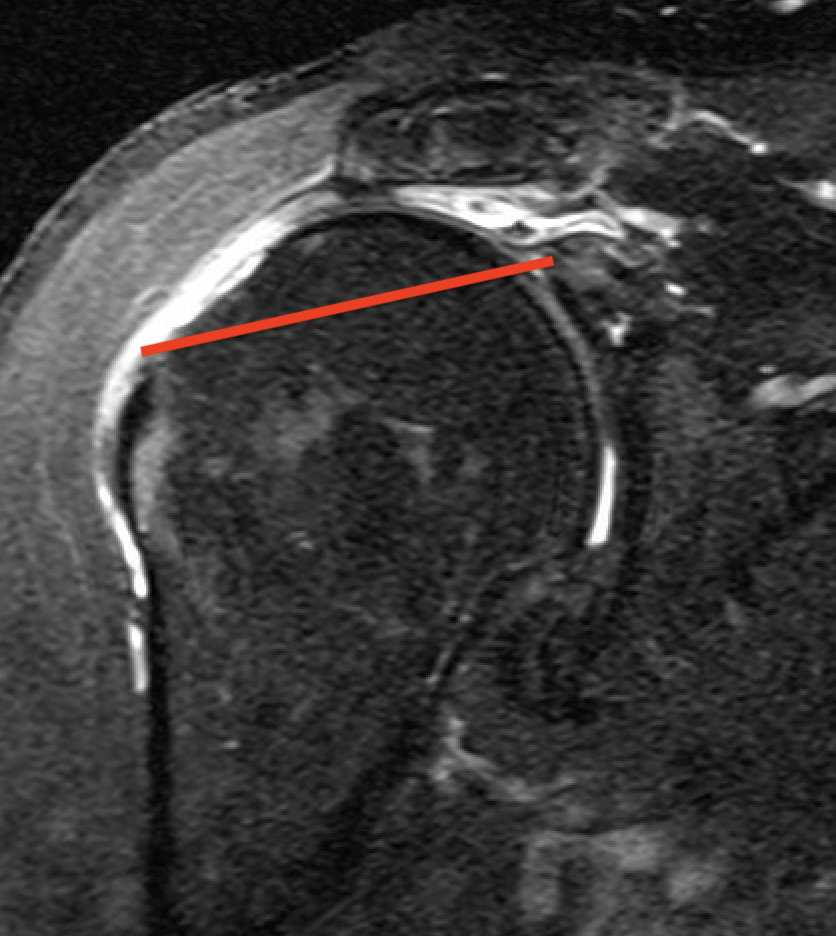

Supraspinatus atrophy

Tangent sign

- sagittal MRI

- line connecting superior coracoid and superior border scapular spine

- if supraspinatus muscle is below line, there is significant atrophy

- positive tangent sign / significant atrophy associated with larger tears / irrepairable tears

Negative tangent / no atrophy Positive tangent / significant supraspinatus atrophy